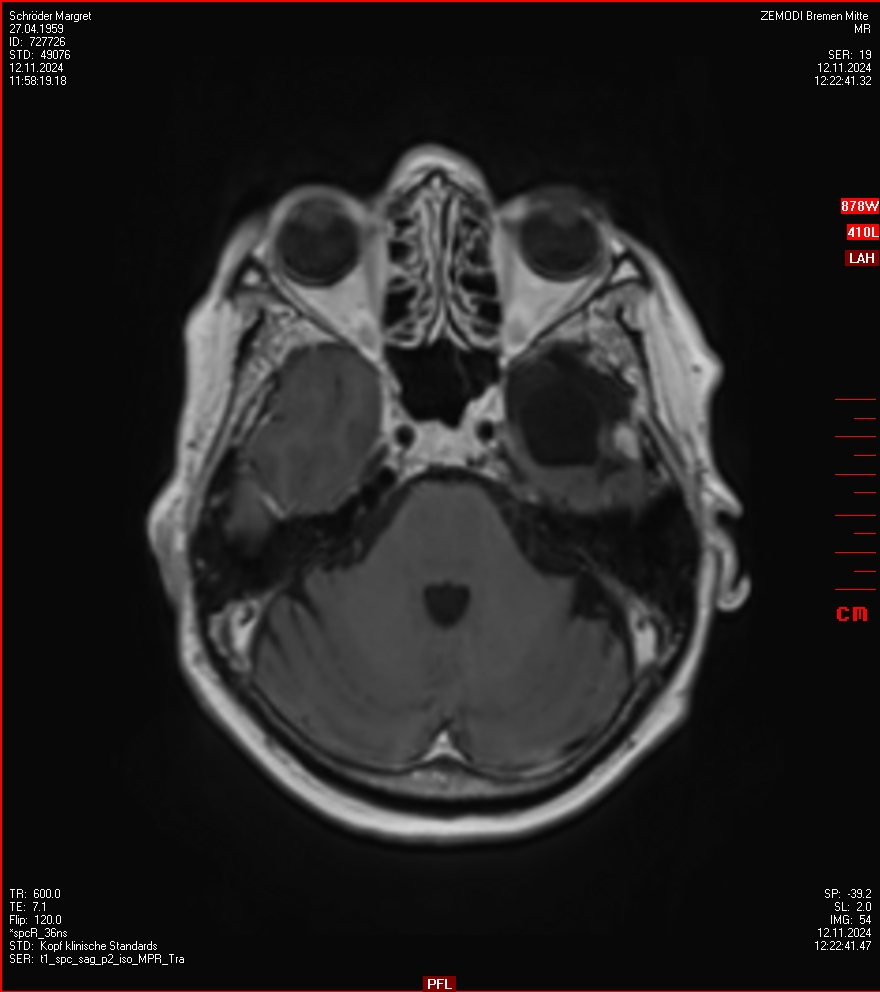

MRT vom 12. November 2024

So nun ein paar neue Bilder aus meinem Kopf. (Durch klicken bekommt man eine größe Ansicht eines Einzelbildes).

Die letzten drei Bilder Zeigen aus meiner Sicht den Tumor, der im Jahr 2021 bestrahlt wurde.